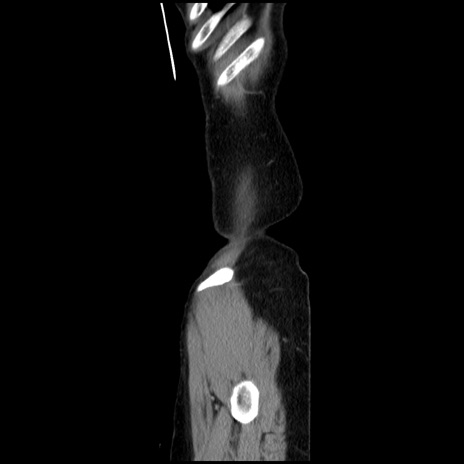

症例32(矢状断像)

【症例】40歳代 女性

【主訴】上腹部痛、嘔気・嘔吐

【現病歴】約9時間前頃から急に上腹部痛、嘔気、嘔吐が出現。改善しないため救急要請。

【既往歴】子宮頚癌(広汎子宮全摘術、放射線療法)、腸閉塞

【身体所見】腹部:平坦、軟、腸雑音亢進、上腹部を中心に腹部全体に圧痛あり。

【データ】WBC 8400、CRP 0.03